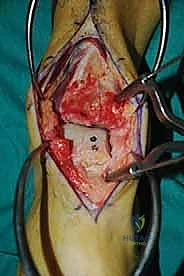

الغوص العميق في جراحة الطعم الخيفي الهيكلي (Structural Allograft Reconstruction)

يهدف هذا الإجراء العبقري إلى استبدال الغضروف والعظم التالفين والميتين بنسيج سليم تماماً مأخوذ من متبرع متوفى (طعم خيفي - Allograft). هذا الطعم يتم تعقيمه وحفظه في بنوك الأنسجة العالمية وفقاً لأعلى المعايير الطبية الصارمة لضمان خلوه من أي أمراض معدية والحفاظ على حيوية الخلايا الغضروفية.

- الترميم التشريحي الحقيقي: يسمح باستعادة الشكل الهندسي الدقيق لعظم الكاحل، بما في ذلك المنحنيات المعقدة لكتف التالوس.